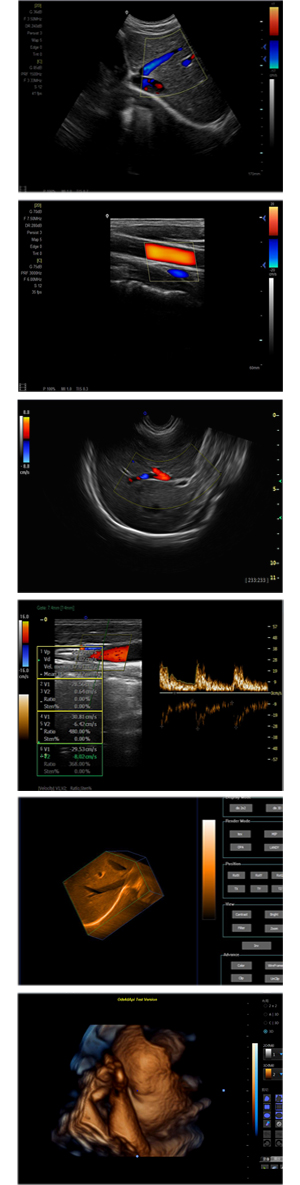

XF-7700型,秉承先鋒彩超技術(shù)之精華,擁有高雅大氣的獨(dú)特外型,為最新一代應(yīng)用型數(shù)字彩色多普勒診斷系統(tǒng),魅力與實(shí)力相融合??蓮V泛適用于腹部、婦產(chǎn)科、心臟、小器官、乳腺、肌骨及外周血管等諸多方面的診查,讓您在臨床超聲診斷應(yīng)用領(lǐng)域得心應(yīng)手,綻放異彩!

突破的成像技術(shù)

● 3D/ 4D成像技術(shù)/選配

● 應(yīng)用于腹部、腎臟、泌尿系統(tǒng)、產(chǎn)科、婦科、盆腔、大動脈、肌肉組織、小器官、乳腺、心臟等

● 能量多普勒成像(PDI)

● 彩色血流量圖(CDE)

● 脈沖頻譜多普勒成像(PW)